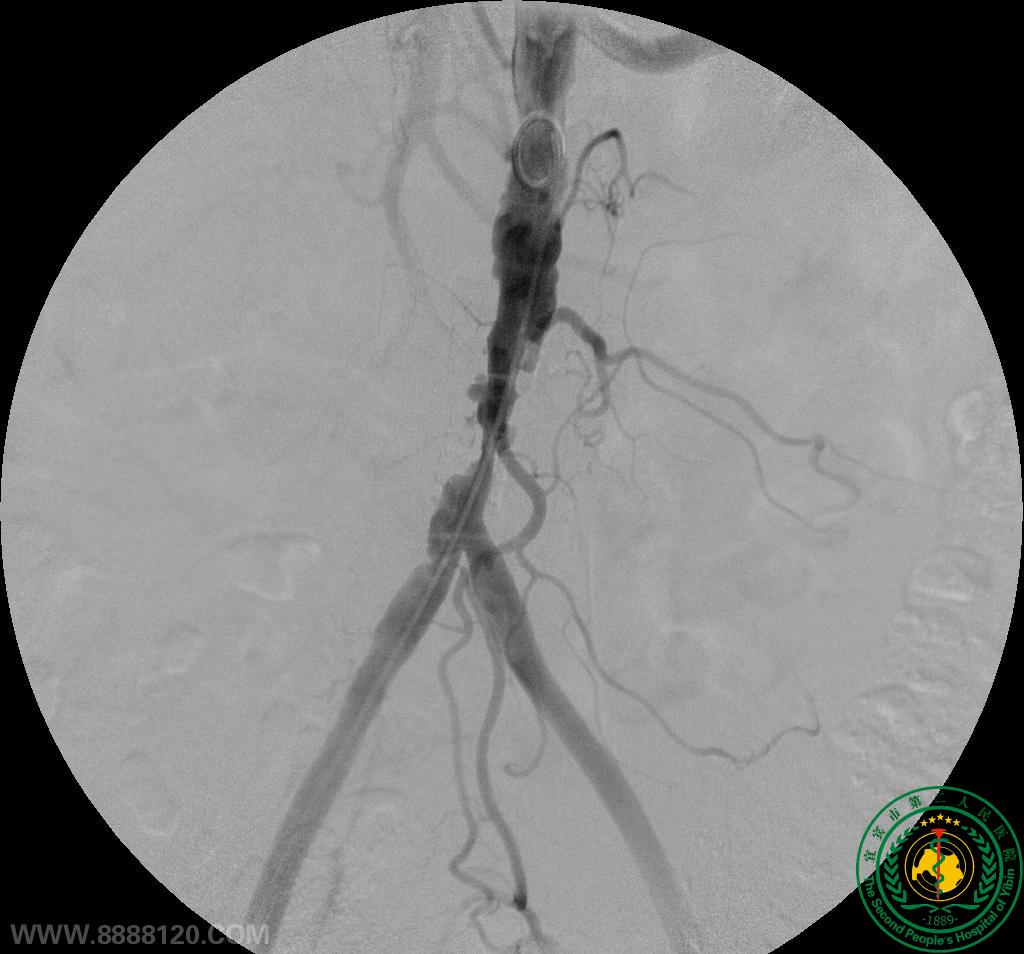

影像科介入室顺利完成一例多发大动脉狭窄的腔内介入手术

影像科介入室顺利完成一例多发大动脉狭窄的腔内介入手术2857